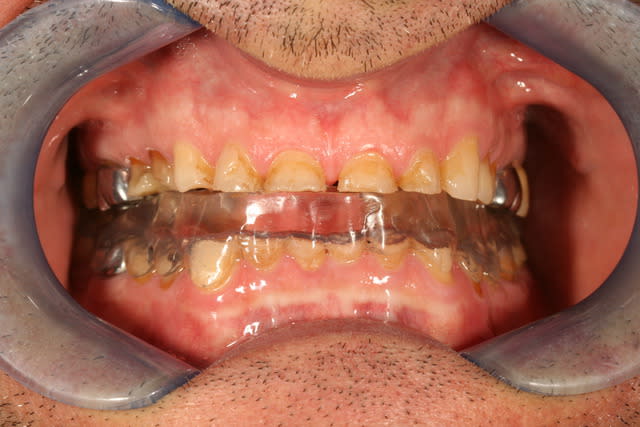

et hop, j'up le post avec quelques news

en vue du tout collé, j'ai fait la reprise d'endo de la 36 et protégé les zones de dentine exposée avec du composite, ça me fait l'IDS pour les futurs collages, je vais a partir de maintenant pouvoir coller à sec ;p

je vous mettrait les photos de la gouttière, mais là je me pose la question de l'augmentation de la DVO, à savoir de combien ?

si je regarde la téléradio de profil, ça me sort une augmentation énorme

si je regarde sa tronche, ça me dit d'augmenter beaucoup

si je regarde les rapports entre les antérieures, faut y aller un max

... bref, ça va me faire une augmentation d'1cm au niveau incisif je pense

du coup la gouttière va être énorme, je pense pas pouvoir la lui faire porter trop longtemps

pareil, j'écoute tous les avis, et je vous tiendrais au courant au fur et à mesure